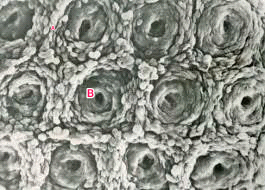

SEM of the Colon

A : Goblet cell B : opening of a crypt *notice absence of villi

SEM of the Colon (side view) A: smooth surface B: Crypts